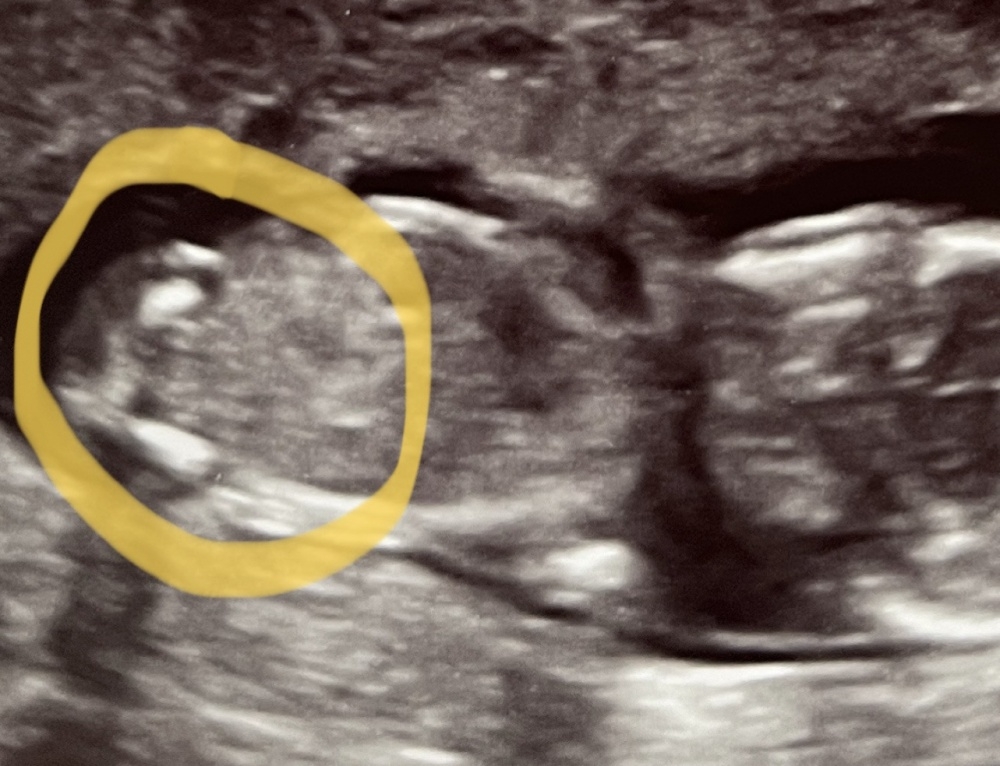

Hallo zusammen, wir waren diese Woche beim Ultraschall (bin in der 18. SSW) und die Ärztin meinte, sie würde auf ein Mädchen tippen, wir sollen aber noch den nächsten Termin Ende September abwarten. Ich kann da ehrlich gesagt nicht viel erkennen, sie meinte man sehe 3 Striche. Was sagt ihr, was seht ihr?

Uns ist es eigentlich eh völlig egal, was es wird, aber jetzt, wo es eine Tendenz gibt, hat mich die Neugierde gepackt 😀

Ich stell euch mal das Bild mit und ohne Markierung rein und freue mich auf Antworten.